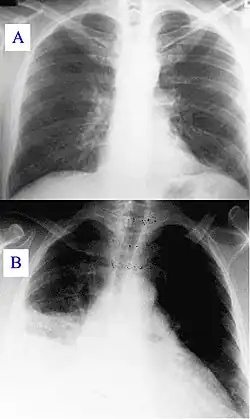

Pendant sa progression, la maladie peut évoluer vers une pneumonie atypique, qui peut mettre en cause le pronostic vital en raison d’un syndrome de détresse respiratoire aiguë (ARDS), de tels symptômes se produisent habituellement pendant les 4 à 5 premiers jours de la maladie.

Signes radiologiques

Pneumopathie atypique